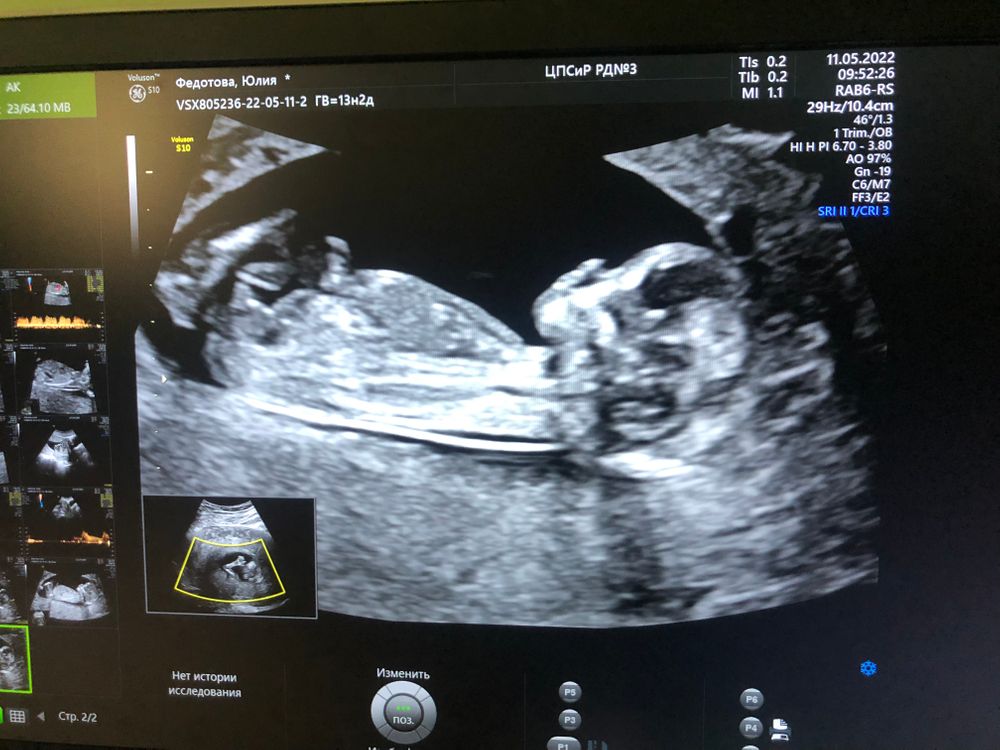

11.05.2022

Подтвердили доченьку😍 Кто у нас?))